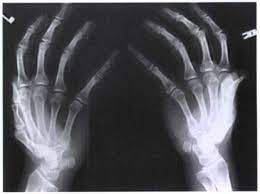

Ball catcher view, also known as Norgaard projection, is a radiograph of hand. It is indicated in assessment of erosive arthropathies e.g., rheumatoid arthritis. Reference: https://radiopaedia.org/articles/hand-ball-catcher-view-1#:~:text=References-,Indications,view%20to%20illustrate%20joint%20erosions. Image via: http://www.radtechonduty.com/2011/12/ap-oblique-bilateral-projection-hand.html